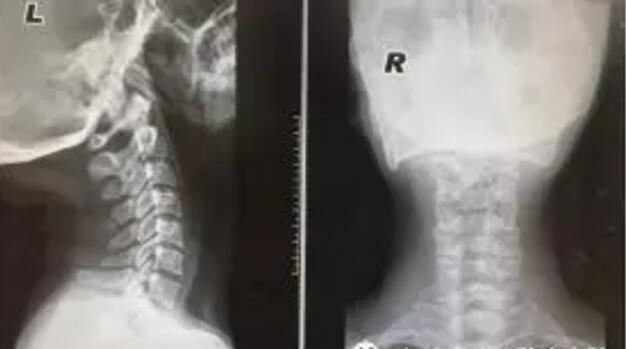

【辅助检查】血常规、肝肾功、ESR(-);颈椎正侧位:颈椎轻度骨质增生。

颈椎MRI平扫:1、颈3-7椎间盘轻度突出。